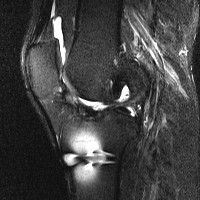

무릎 mri 간단히 봐주실 수 있으시나요 ㅠㅠ

안녕하세요 8년전 십자인대 수술하고 최근 무리한 운동에 무릎 불편감이 생겨서

mri 찍었습니다.

진단결과는 첫 찍은 병원에서 활액막염 이라는 진단을 받았습니다. 혹시 봐주실 수 있으실까요?

올라온 MRI가 단편적이라서 정확한 진단에 어려움이 있지만 십자인대에는 큰 이상이 있지는 않은것 같으며, 무릎관절내 물이 있는 것으로 보아 활액막염의 진단이 맞을 것 같습니다.

하지만 단편적인 영상이기 때문에 촬영병원에서 정확한 판독지 등을 받으시는 것이 좋겠습니다.